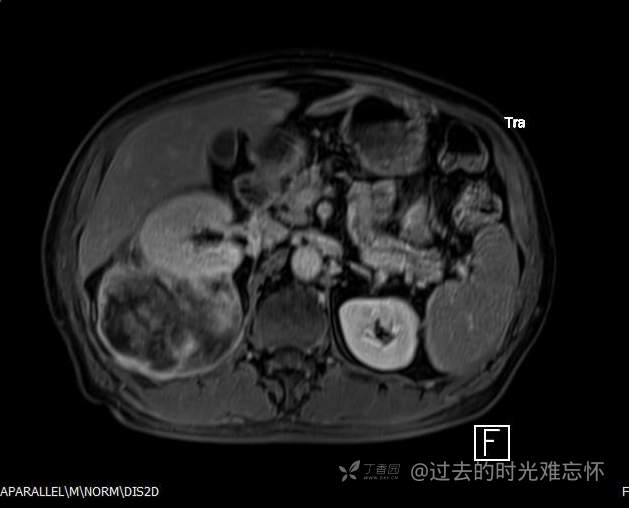

增强

患者性别:男

患者年龄:73岁

主诉:咳嗽1月余。曾有血尿一次。后背部酸痛不适1-2年左右,无明显消瘦。

辅助检查:CT MRI

临床诊断:占位

黏液样脂肪肉瘤 (12)